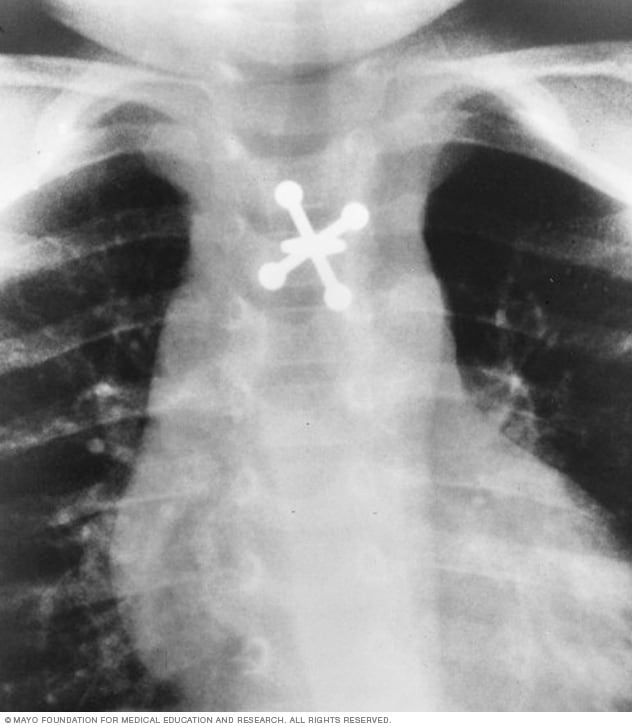

بالصور أغرب ما رصدته أشعة إكس راي داخل بطون مرضى

جريدة الرياض أغرب صور الأشعة السينية